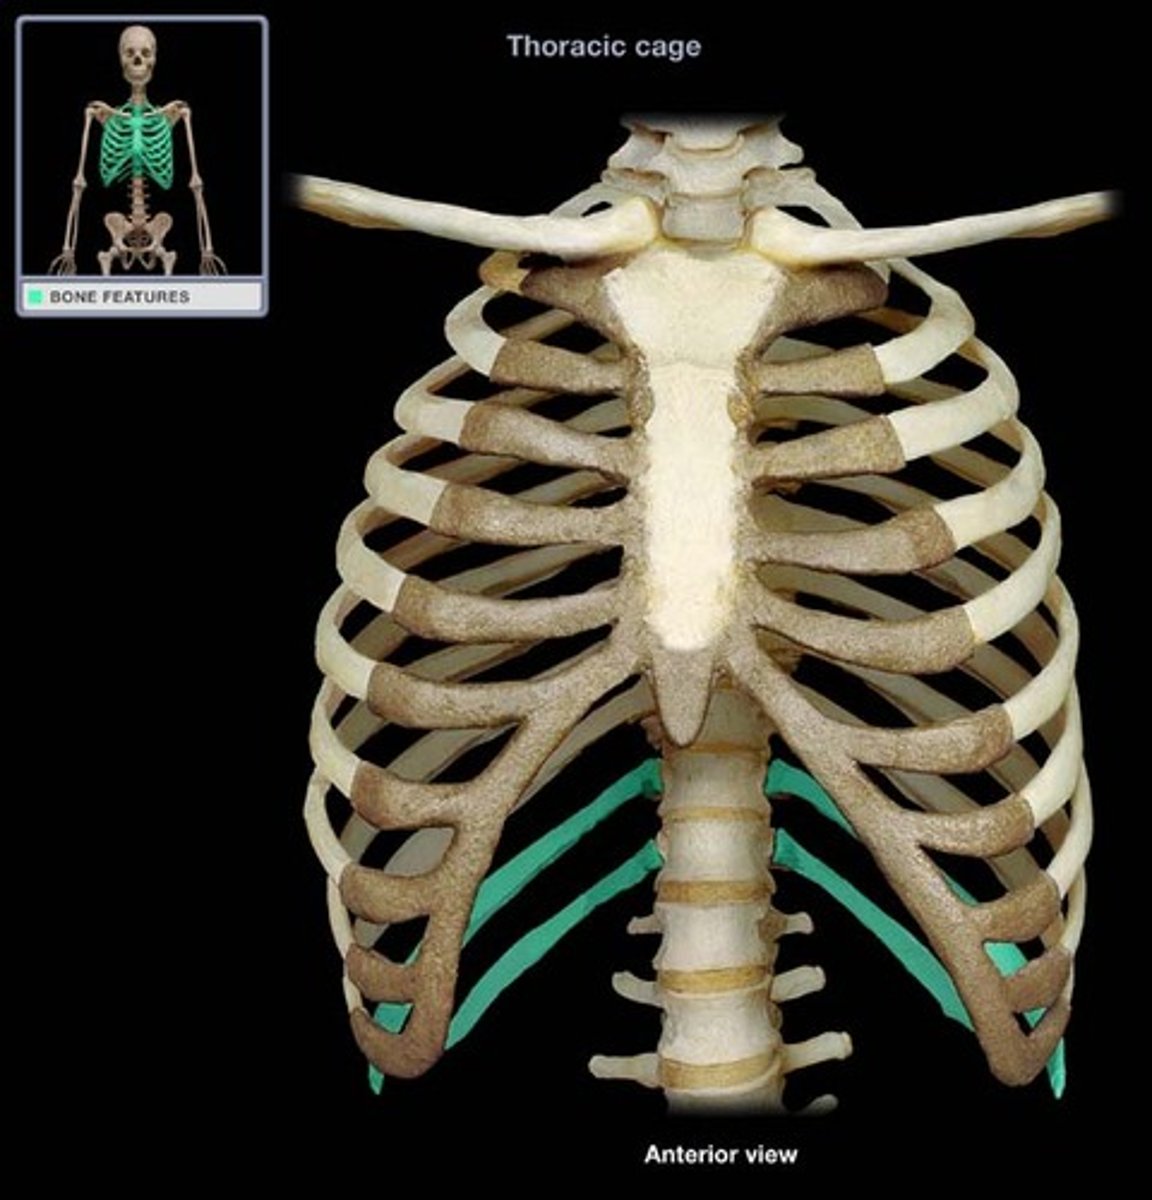

floating ribs

11-12

costal cartilages

What is this structure?